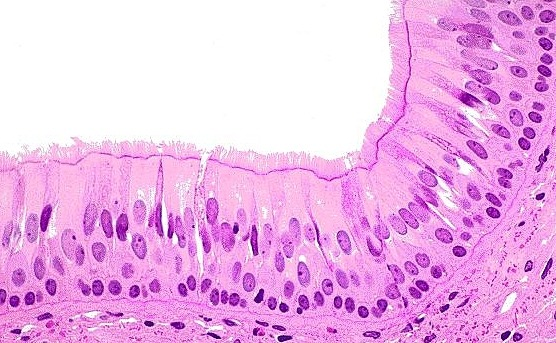

Pseudostratified ciliated columnar epithelium

apical surface

top of image

basal surface

bottom of image no purple

basement membrane

purple part

goblet cell

secretes mucus, typically found in the respiratory and gastrointestinal tracts

cilia

top part hair like